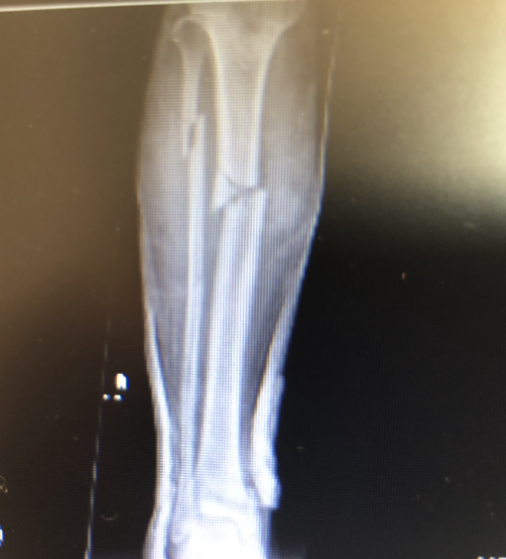

Working circumstances on the fishing vessels are sometimes horrendous and dangerous with frequent storms working day and night in the southern ocean. During my watch severe handinjuries were common and one weekend the SAR helicopter needed to evacuate four severly injured fishermen. Upon arrival to the hospital one fisherman was dead due to hypothermia (thrown overboard but saved back onboard), and three were severly injured with ribfractures,hole in the lung,lower limb fractures,compartment syndrome,hip dislocation etc, and emergency surgery was ongoing the whole day. When these young men (mainly Indonesians 25-30 years in age) woke up from anesthesia there first question was when they could be back on their ship for work. In all Scandinavian countries it´s on the contrary and when digging deeper into the subject I learned to know that if these fishermen (who sign up for 400days at sea) loose even one day at work they risk getting paid NOTHING !